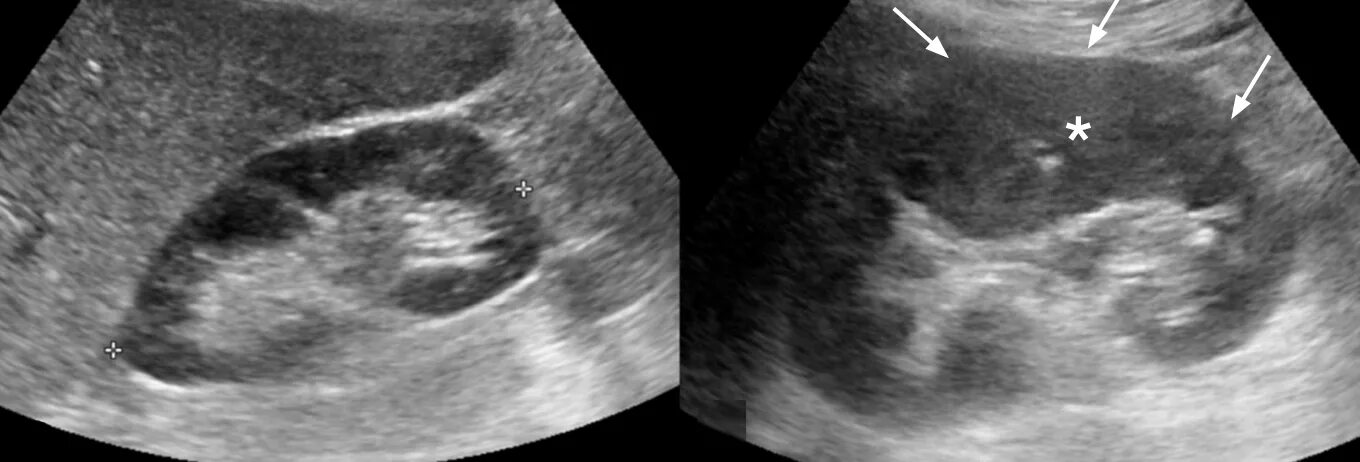

Кальцинат узи